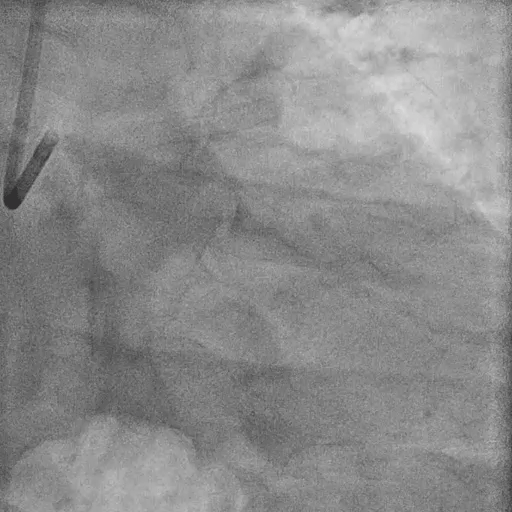

Final Angiography

Excellent vessel expansion and blood flow